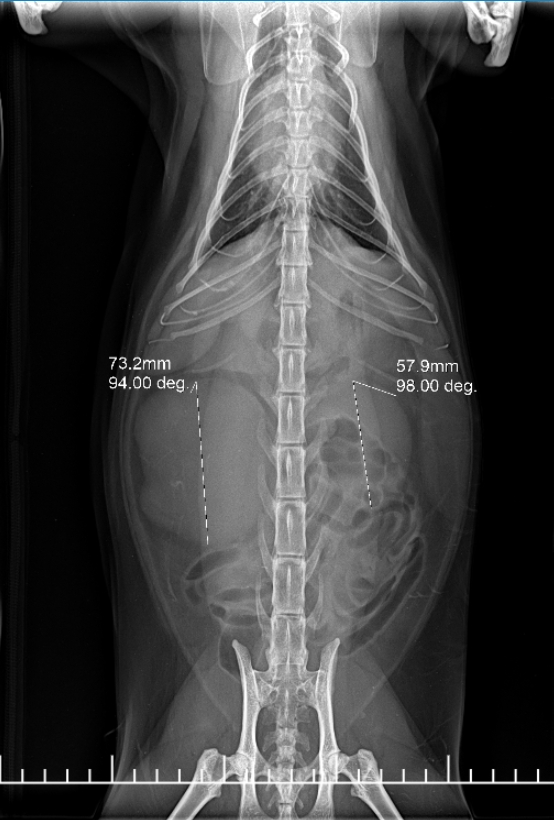

- 影像學檢查 (Imaging) 利用 X 光與超音波,精確定位腫瘤位置,並檢查是否侵犯周邊組織或發生轉移。